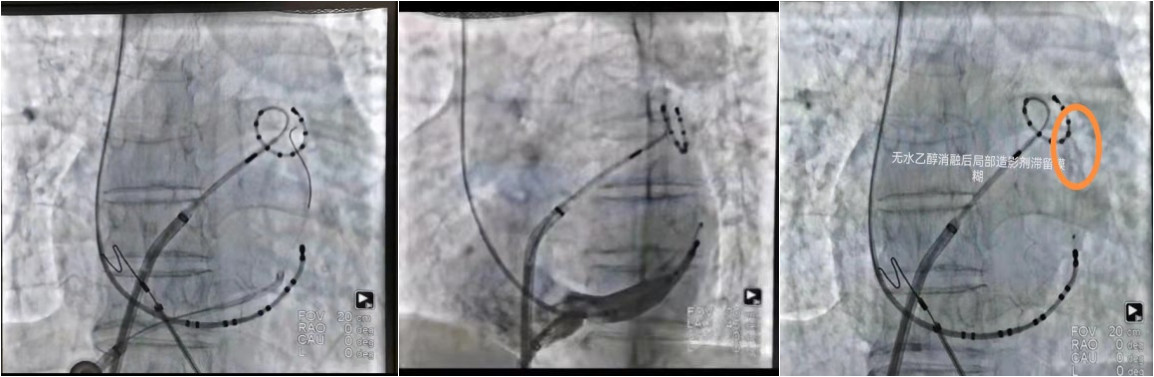

术中,手术团队首先房间隔穿刺将环肺标测电极放置肺静脉前庭,发现较大电位,随后经股静脉将导管送至冠状窦内造影见Marshall 静脉显影,沿PTCA导丝将OTW球囊送入Marshall静脉内,扩张封堵后经中心腔将无水酒精缓慢注Marshall 静脉内,在Marshall 静脉远段注射2ML、近段注射3ML,内膜面呈低电压,CS1-2电位变小。

利用Ensite三维成像重建左房并行电压标测,再行两侧肺静脉消融,房颤转为二尖瓣峡部房扑,行二尖瓣峡部瓣环侧消融,转为三尖瓣峡部房扑,消融三尖瓣峡部,转为窦律!各消融线双向阻滞,手术成功。